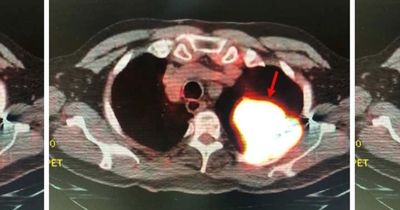

Ученые разработали модель искусственного интеллекта, которая по стандартным КТ-снимкам способна выявлять признаки хронического стресса и оценивать связанный с ним сердечно-сосудистый риск. Анализируя объем надпочечников на уже имеющихся изображениях, ИИ фиксирует накопленное воздействие стресса на организм. Это более информативная альтернатива анкетам и разовым лабораторным измерениям.